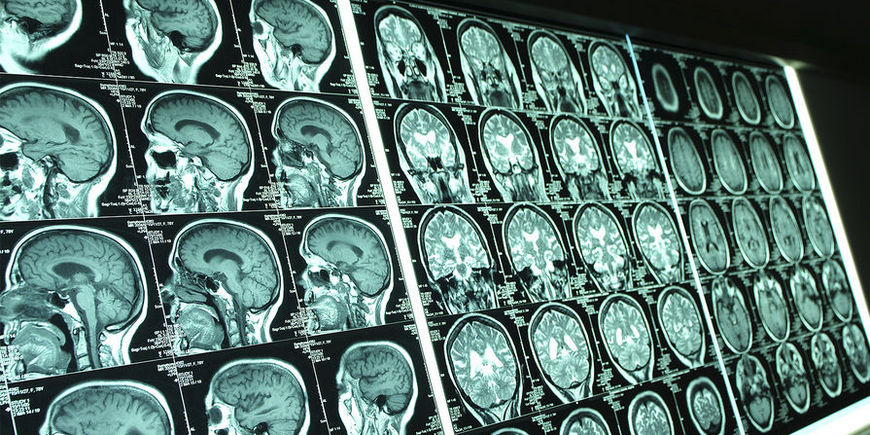

В рамках оценки психического состояния пациентки врачи также провели МРТ. Оно и выявило настоящую причину появления голосов свыше – опухоль головного мозга, злокачественную глиому.

Ранее не отличавшаяся особой религиозностью женщина часами штудировала Библию и другие священные книги. Близкие друзья и родственники предположили, что у женщины так могла проявляться депрессия — в тот период она заботилась о страдавшем от рака родственнике. Однако результаты МРТ выявили несколько пораженных участков в мозге. Биопсия показала, что у пациентки глиобластома.